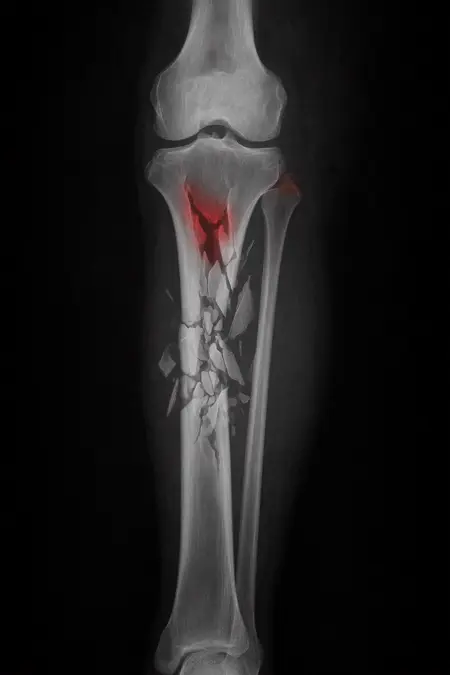

アートや写真の編集用に設計されたFlux Kontextのようなモデルを、医療画像、たとえば「単純な」骨折の赤色マーキングに使用できるか?

即答:面白い結果を出すが、過剰に反応し、医療ツールとしては信頼性に欠ける。これはアイデアを試すためのプロトタイプに過ぎない。

さらに攻撃的な設定(例:rk beta57、Denoise 1.0)では、**偽陽性100%、検出100%**という馬鹿げた結果に:すべてを赤で塗りつぶし、健常部もほぼすべて骨折と誤認する。未経験の目には区別がつかない。

Civitai用に作成した、100% AI生成の合成ミニデータセット(健康なX線10枚、骨折のあるX線10枚)でテスト:

- 健康な骨での偽陽性:100%

- 骨折検出:≈ 45%

不適切な用途

- 重大な診断には使用しない

- 医師の代わりにはならない、まったくもって!

このLoRaは視覚的実験用のみです。

医療機器ではありません。信頼性がなく、臨床診断には使用しないでください。